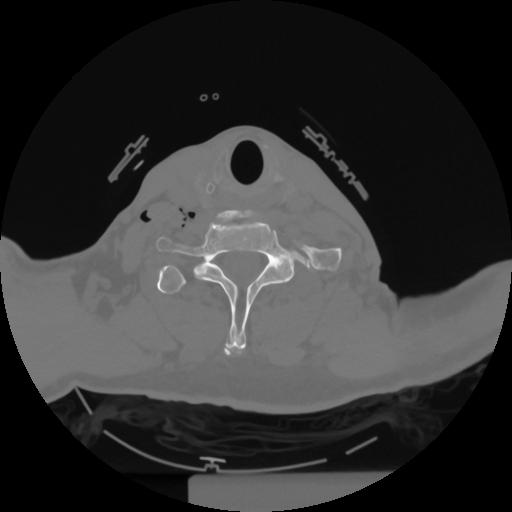

12 P.BLANDAS,,Vol,0.5,P.BLANDAS,,